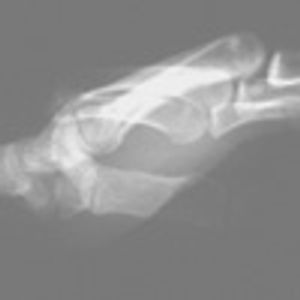

After a fall during a soccer match 2 weeks earlier, a 26-year-old woman had pain of the right midfoot, with moderate swelling. The pain was aggravated with a normal gait and alleviated with an antalgic gait, specifically with inversion of the right ankle such that most of the weight from heel-strike through toe-off transmitted forces from the lateral calcaneus through the fifth metatarsus to the fifth phalanx.